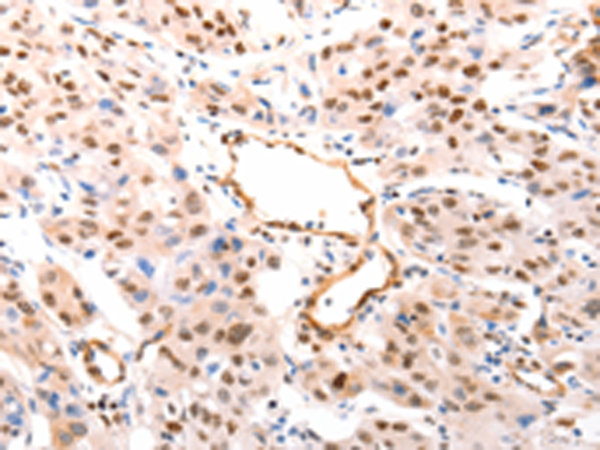

分类: 科研抗体货号: P04531别名: MCH6; APAF3; APAF-3; PPP1R56; ICE-LAP6; CASPASE-9c应用: IHC反应种属: Human, Mouse